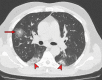

Chest CT has a potential role in the diagnosis, detection of complications, and prognostication of coronavirus disease 2019 (COVID-19). Implementation of appropriate precautionary safety measures, chest CT protocol optimization, and a standardized reporting system based on the pulmonary findings in this disease will enhance the clinical utility of chest CT. However, chest CT examinations may lead to both false-negative and false-positive results. Furthermore, the added value of chest CT in diagnostic decision making is dependent on several dynamic variables, most notably available resources (real-time reverse transcription-polymerase chain reaction [RT-PCR] tests, personal protective equipment, CT scanners, hospital and radiology personnel availability, and isolation room capacity) and the prevalence of both COVID-19 and other diseases with overlapping manifestations at chest CT. Chest CT is valuable to detect both alternative diagnoses and complications of COVID-19 (acute respiratory distress syndrome, pulmonary embolism, and heart failure), while its role for prognostication requires further investigation. The authors describe imaging and managing care of patients with COVID-19, with topics including (a) chest CT protocol, (b) chest CT findings of COVID-19 and its complications, (c) the diagnostic accuracy of chest CT and its role in diagnostic decision making and prognostication, and (d) reporting and communicating chest CT findings. The authors also review other specific topics, including the pathophysiology and clinical manifestations of COVID-19, the World Health Organization case definition, the value of performing RT-PCR tests, and the radiology department and personnel impact related to performing chest CT in COVID-19. ©RSNA, 2020.